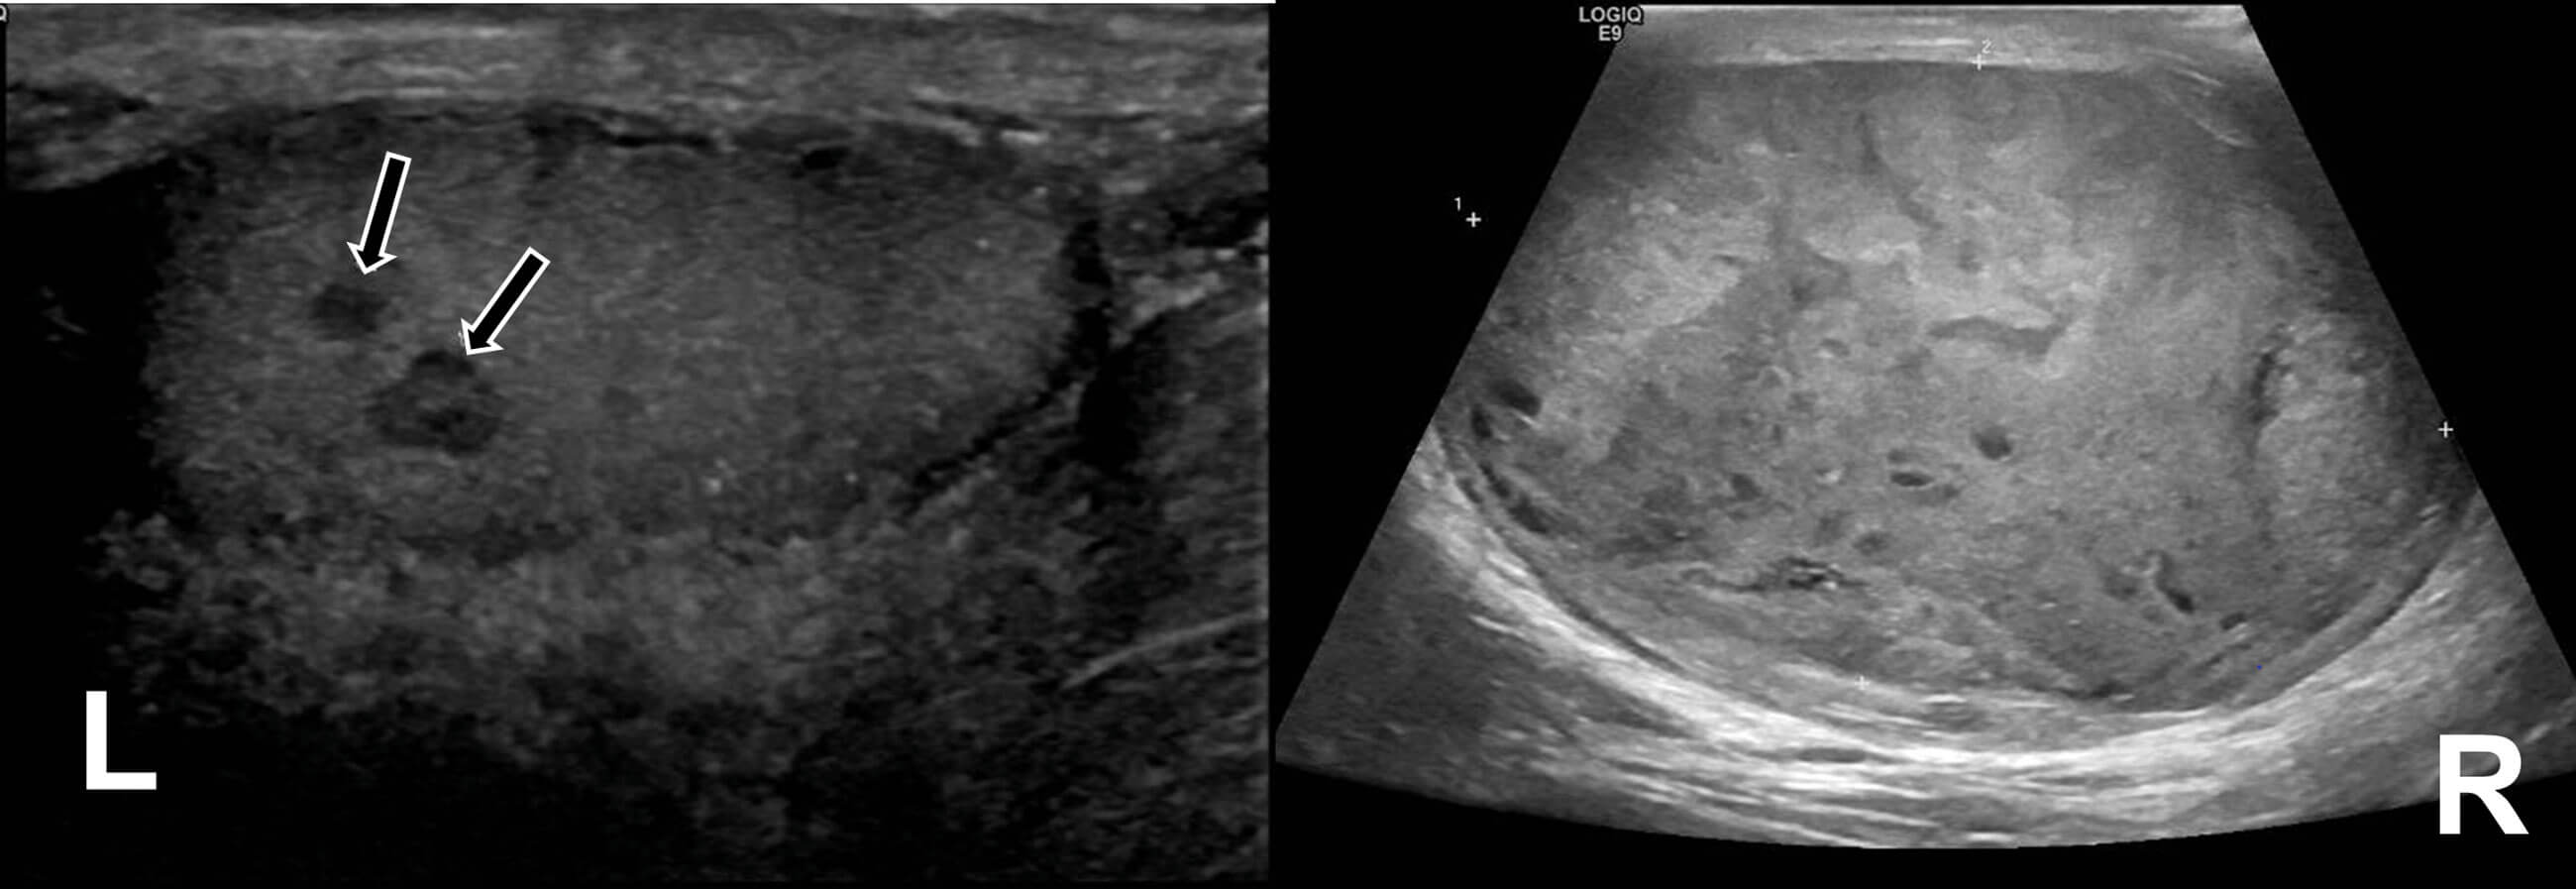

On examination, the right testicle was globally irregular, with the left atrophic and difficult to examine. US of the testes showed a grossly abnormal right testicle, measuring 92 x 53 x 60mm, and two small lesions with vascularity in the upper pole of the left testis concerning for malignancy (Figure 3).

Figure 3: Two abnormal areas on the left atrophic testis arrowed (L) and grossly abnormal right testicle (R).